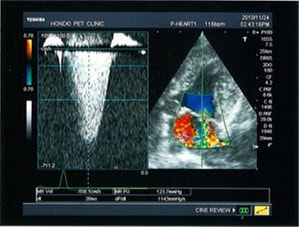

A:超音波カラードップラーでの僧帽弁逆流速度の測定

B:E波とA波の測定

C:僧帽弁逆流の動画(大きく表示させたい場合は、ココをクリックして下さい。)